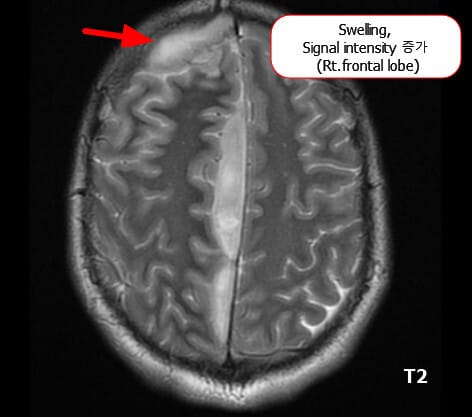

주요 MRI 소견

세균성 수막염에서는 조기 진단과 합병증 파악을 위해 MRI를 시행합니다.

🔵 뇌부종(Cerebral Edema)

염증 반응으로 뇌 조직에 부종이 발생할 수 있습니다. 특히 확산강조영상(DWI)이나 T2/FLAIR에서 고강도(high signal intensity)로 나타납니다.